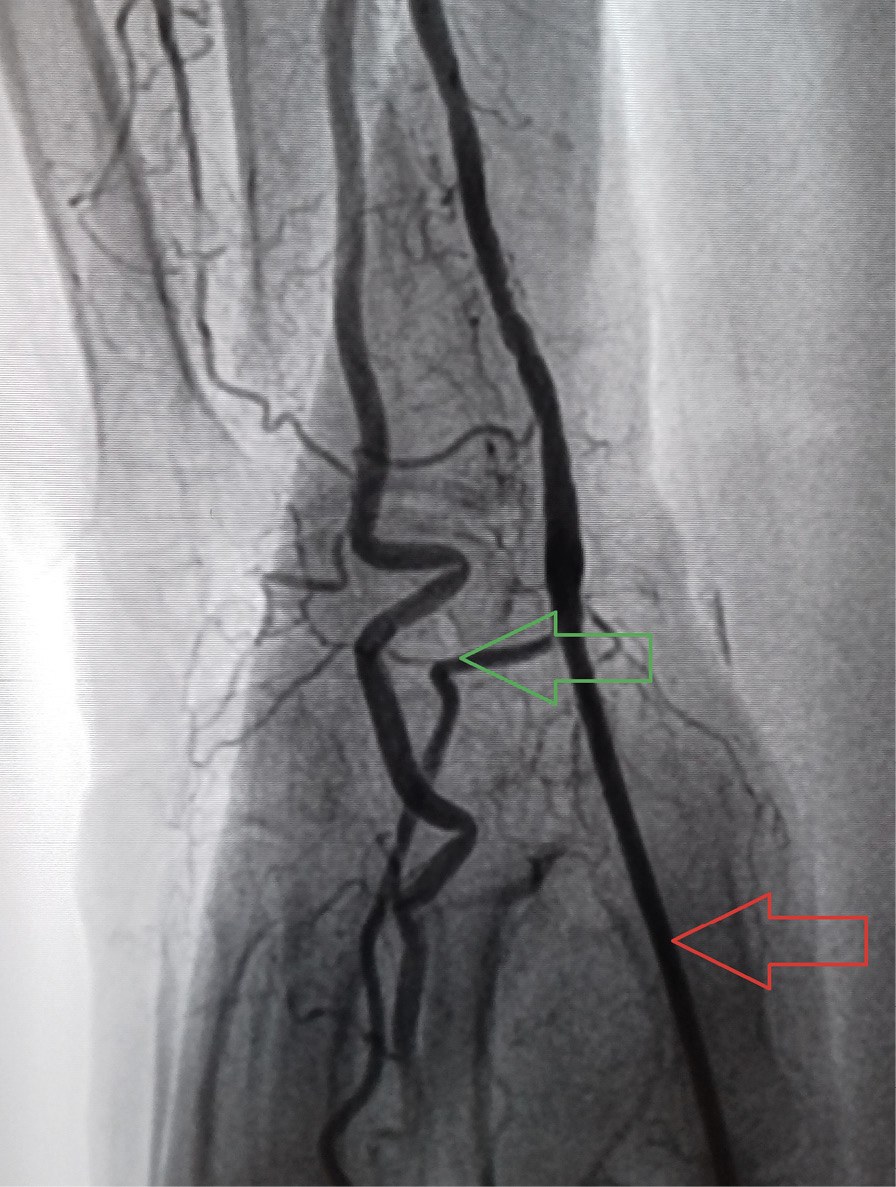

По данным осмотра, пальпации и УЗИ артерии доступа, проведенных на 5–7-е сутки после вмешательства, псевдоаневризма лучевой артерии отмечалась у 3 (3%) пациентов из группы ТРД, в группе ДпЛД данное осложнение выявлено не было. Случаев развития артериовенозных фистул в зоне доступа не отмечено ни в одной из групп. ОЛА предплечья выявлена у 3 (3%) пациентов группы ТРД. В группе ДпЛД случаев ОЛА предплечья выявлено не было. ОЛА дистальных отделов с сохранением кровотока в лучевой артерии предплечья («дистальная» ОЛА) отмечалась у 3 (3%) пациентов в группе ДпЛД (рис. 4). Кровоток в лучевой артерии предплечья при этом был сохранен. Случаев развития дистальной ОЛА у пациентов группы ТРД выявлено не было. Учитывая малый объем наблюдений, предикторы ОЛА, гематом и псевдоаневризм выявить не удалось. При этом все 3 (100%) случая ОЛА предплечья и 2 (66,6%) случая дистальной ОЛА были отмечены у пациентов женского пола. Следует отметить, что ни в одном из 6 случаев конверсии доступа (5 случаев ДпЛД и 1 ТРД) не было выявлено ОЛА предплечья и дистальных ОЛА «больших» гематом 3–5-й степени по шкале EASY, а также артериовенозных фистул. Помимо оценки состояния лучевой артерии у всех пациентов, включая пациентов с конверсией ТРД и ДпЛД, оценивали диаметр лучевой артерии на уровне предплечья и дорсальной поверхности ладони по данным УЗИ (табл. 4). Диаметр лучевой артерии на предплечье был значимо выше диаметра на дорсальной поверхности ладони у пациентов в обеих группах, независимо от типа выбранного доступа (2,75 ± 0,32 и 2,38 ± 0,36 мм в группе ТРД, p < 0,001; 2,84 ± 0,38 и 2,45 ± 0,36 мм в группе ДпЛД, p < 0,001). В то же время у пациентов с конверсией доступа диаметр лучевой артерии на обоих уровнях был ниже средних значений. Однако из-за малого количества наблюдений (1 пациент из группы ТРД и 5 пациентов из группы ДпЛД) статистически значимых различий выявить не удалось.

Рис. 4. Окклюзия дистальных отделов лучевой артерии по данным выполненного на 5-е сутки ультразвукового исследования артерии доступа (указана красной стрелкой), кровоток в поверхностной ладонной ветви лучевой артерии (указана зеленой стрелкой) сохранен [17]